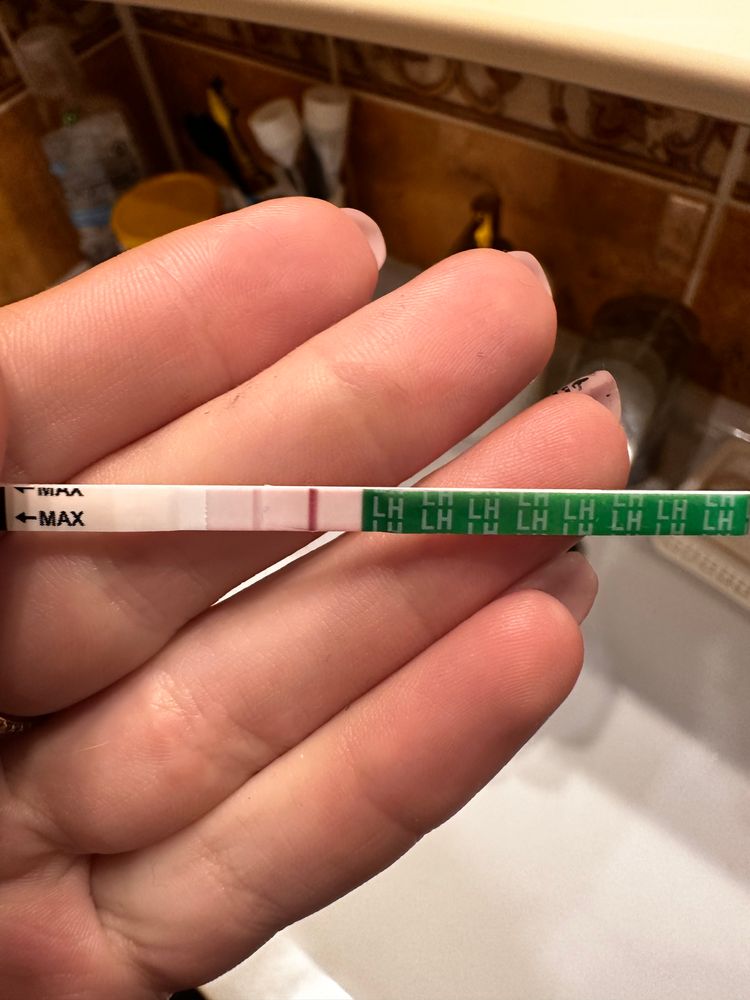

Девачки, почитала всех и короче пошла тесто манить , не могу уснуть теперь 😂😂😂😂 во что получилось напоминаю на 6 дпо

тест на о сегодняшний

Тест с верху старый 2 цикла назад

Алина Горева, что-то есть, но мне кажется тест потек(

у меня в беременность именно тесты на овуляцию показали жирные // , сделала тест на б и была еле заметная полоска . Сейчас прикреплю . Но к сожалению замерла на 6 Нед